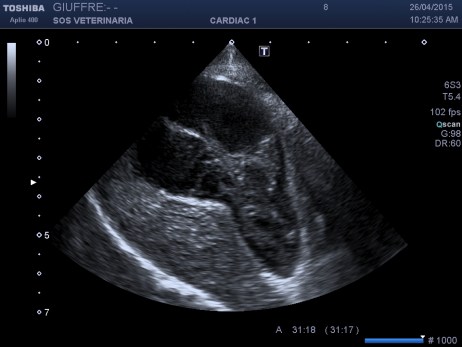

Cane femmina di bassotto di 6 aa presentata al pronto soccorso con vomito incoercibile ,profondo abbattimento ,mucose subitteriche ,no febbre,addome palpabile ,insorgenza dei sintomi iperacuta, l’ecografia addominale ha focalizzato una colecistopatia caratterizzata da severa distensione dell’organo , contenuto interno incrementato in ecogenicita’con formazione di una figura ecogena irregolare a pattern stellato (tipo Kiwi ) maggiormente evidenziabile con la sonda lineare frequenza ,pareti normali ,lieve falda di fluido tra parete e fossetta epatica ,evidente ectasia del dotto biliare comune , dotto cistico non evidenziabile per il grado di distensione elevato della coleciste ,nessun pattern riferibile a pancreatite o neoplasie della papilla,.il doppler colore evidenziava nei vasi portali un flusso a mosaico, che non scompariva all’aumento del PRF la mancata pulsatilita’ del pattern lo distingueva dal fenomeno dell’arteriolarizzazzione comune nelle epatiti tuttavia tale flusso non descritto in letteratura indicava certamente un’alterazione vascolare del parenchima come poi ha confermato il decorso clinico e non una semplice colastasi La ceus ha confermato la natura avascolare del contenuto e non ha fornito ulteriori indicazioni